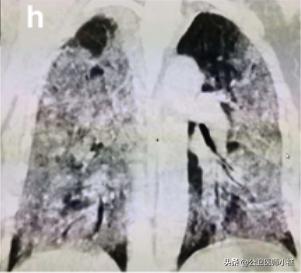

如果治疗不及时,或者免疫力无法抵御病毒,则很可能威胁生命,发展为白肺。

白肺,肺部恶化

当然白肺在仅仅发生在极少数弥漫性肺部损伤且涉及多个肺叶的危重型患者。

在此阶段,患者肺通气功能严重受损需要持续性吸氧,甚至需要进行体外膜氧合(ECMO)俗称人工肺。